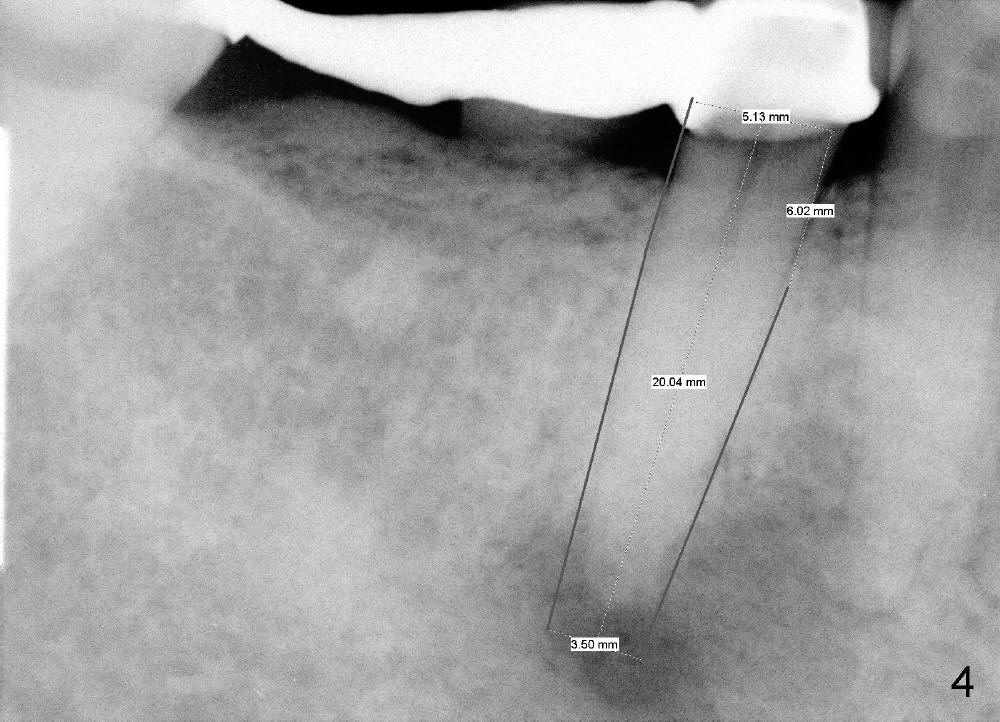

If the immediate implant (5x20 mm) is placed within the confinement of the socket, the integrity of the nerve will be not violated (Fig.4). The patient returns for the surgery 2 months after bridge removal. The root stump is cleaned so well that the buccal apical fistula disappears (Fig.5). The mesiodistal dimension of the root is 5 mm, whereas buccolingual 6.5 mm. Infiltration (not block) anesthesia is administered. The root is extracted. A 2 mm pilot drill drops by itself into the socket (Fig.6 D); the loop should overlap the apex of the socket.